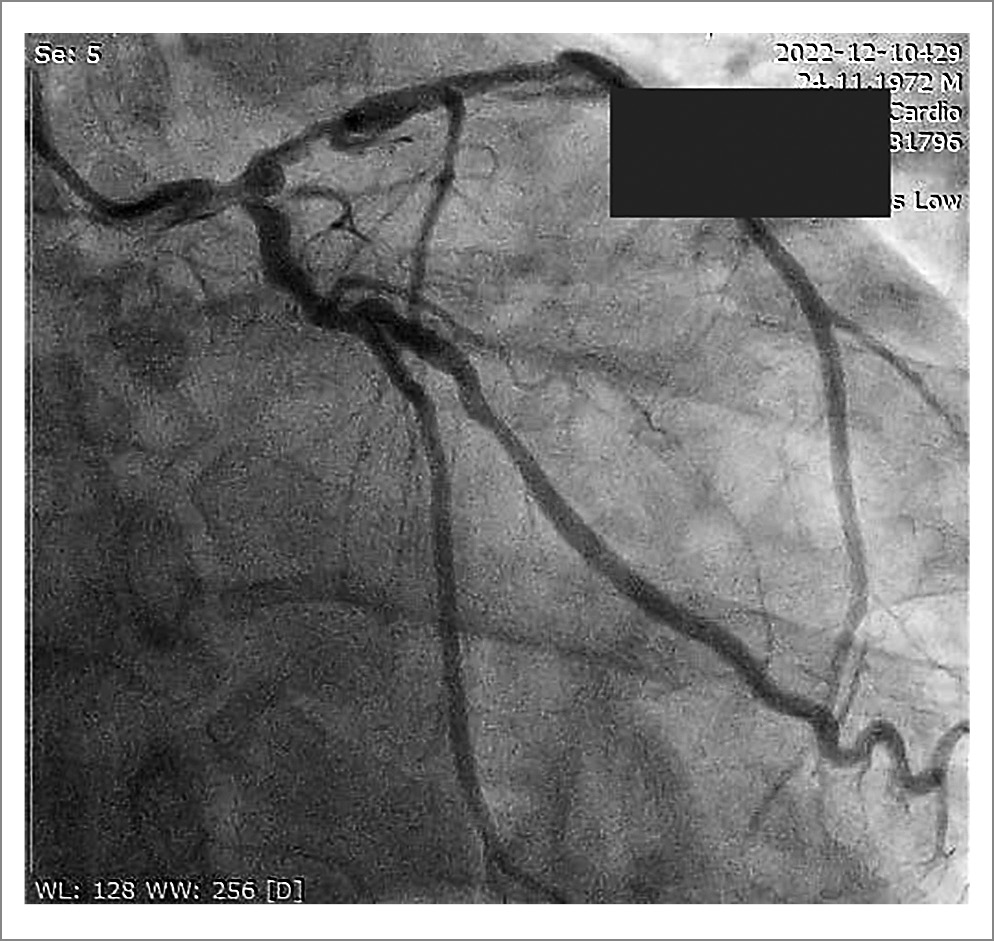

По данным коронарографии (КАГ) у пациента имелось многососудистое поражение коронарных артерий (КА) с критическим стенозом передней нисходящией, 1-й диагональной и огибающей артерии (рис. 5). Подробное описание КАГ представлено в табл. 2.

Рис. 5. КАГ пациента

Таблица 2. Данные КАГ

Артерия | Степень поражения |

Ствол левой КА | Стеноз в терминальном сегменте (60–65%) с переходом в устья ПНА и ОА |

Передняя нисходящая артерия | Стеноз в устье (30%); протяженный стеноз в проксимальном сегменте (80–90%) |

Первая диагональная артерия | Субтотальный стеноз в проксимальной трети |

Огибающая артерия | Стеноз в устье (80–90%); стеноз проксимального сегмента (70–80%) |

Артерия тупого края | Стеноз в устье (50%) |

Правая КА | Стеноз в проксимальном сегменте (50%); стеноз среднего сегмента (40–50%) |

Примечание. ПНА – передняя нисходящая артерия, ОА – огибающая артерия.